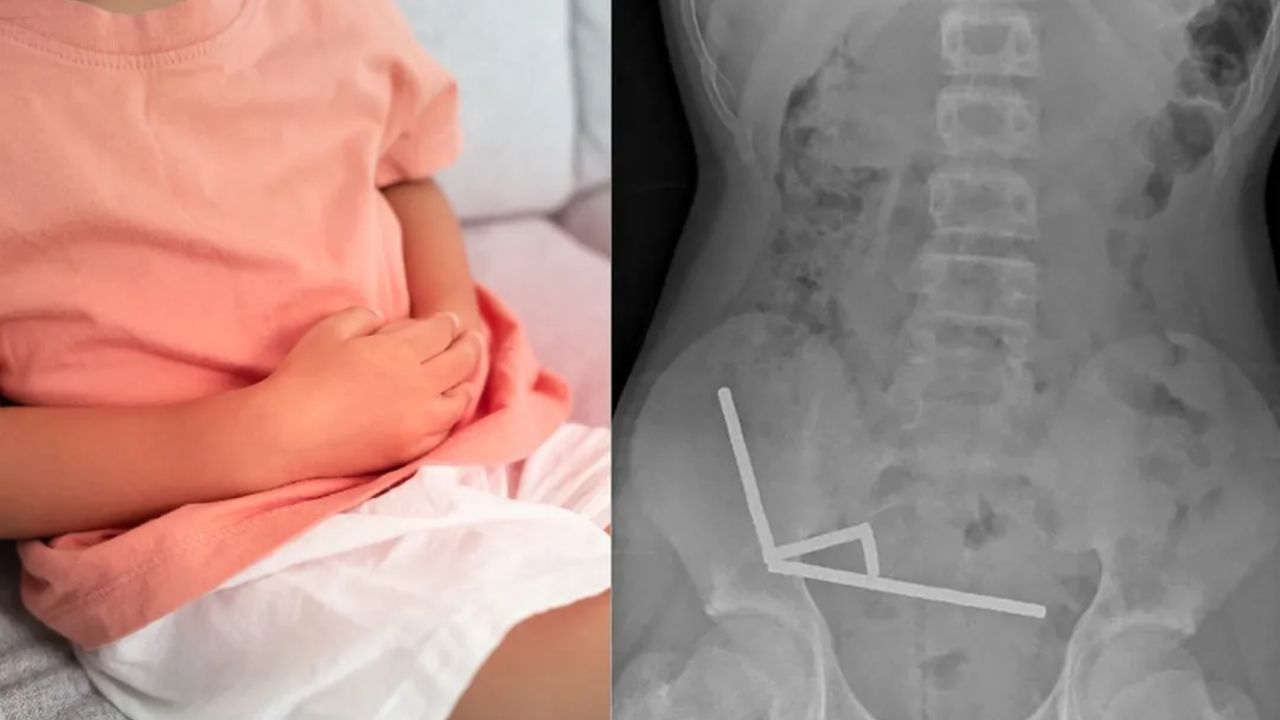

Röntgen görüntülerinde, çocuğun bağırsaklarında zincir halinde dizilmiş metal toplar tespit edildi. Ameliyatta bu mıknatısların ince bağırsak ve çekumda birbirine yapışarak kan akışını kestiği ve “basınç nekrozu” denilen doku ölümüne yol açtığı ortaya çıktı.

Doktorlar, zarar gören bağırsak kısmını almak zorunda kaldı. Genç hasta sekiz gün sonra taburcu edildi.